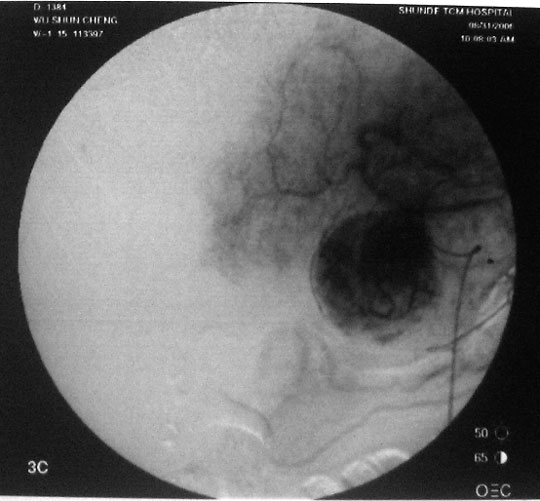

介入治疗过程:右股动脉穿刺,引入导丝导管,超选入肝固有动脉,造影显示肝右动脉肿瘤供血,圆球样肿瘤边界清楚。采用同轴导管进一步超选入右肝动脉、肿瘤血管边缘,注入化疗药+碘油混合剂7ml。

图1-3:导管进入肿瘤血管后造影,分别显示造影早期、中期、末期肿瘤情况。

图4:栓塞治疗后,肿瘤已为化疗药+碘油混合剂充填。